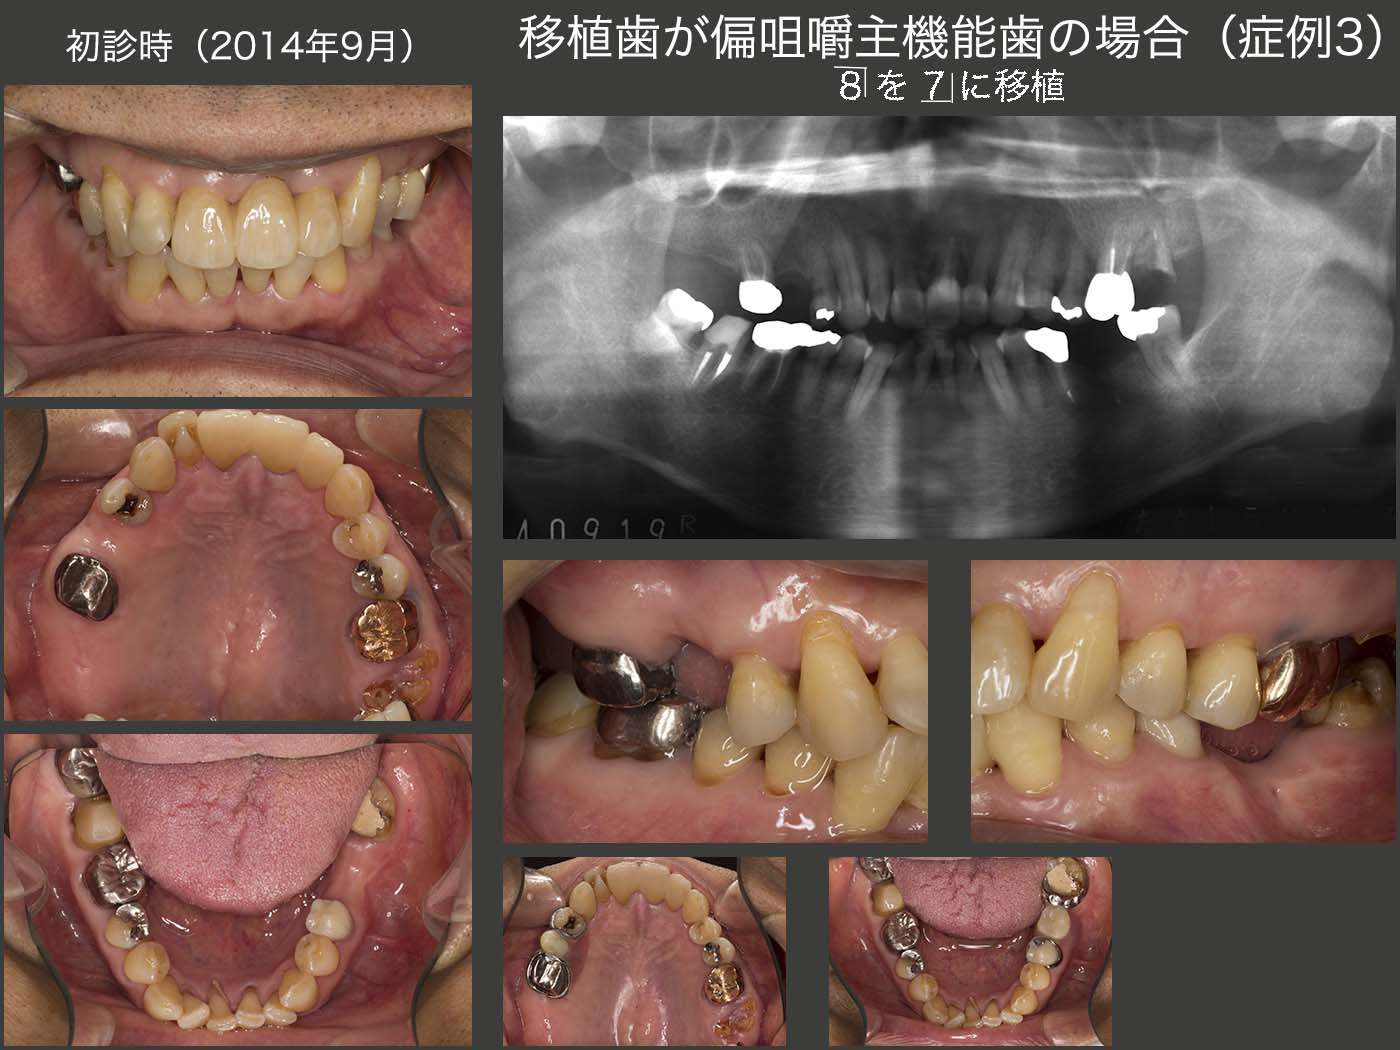

12.移植歯が偏咀嚼主機能歯の場合(症例3)

2014年9月初診,72歳男性.主訴は,左上7が他院で抜歯と言われたが,何とか残してほしいとのこと.右上6は口蓋根がヘミセクションされており,また右上5,7を喪失していた.一応義歯が装着されているが,この患者さんは左側で主に咀嚼しており,その結果左上7の歯根破折に至ったと推測した.確かに左上7は残根状で保存する価値があるかどうか迷ったが,とりあえず歯周基本治療を行い,まずは信頼関係の構築に努めた.

最終的には右側の咬合支持を増すために,右下8を右上7部に,左上7の口蓋根を右上5部へ移植することにした.なお右下8に挻出力を加え,歯根膜を傷つけずに抜歯しやすいように工夫した.2015年3月に移植を行った.なお,移植された右上7が咬合平面より大分低位に位置してしまったため,6月5日に矯正的挻出を施し,7月22日に終了した.

移植の術前,術後と患者さんは左側咬みを余儀なくされたため,2015年8月,左側の咬合支持歯である,左下5に歯根破折が生じてしまった.そこで左下7にコーヌス冠,健全歯である左下4にはクラスプを用いた義歯を製作した.

左上7の頰側根は,16年1月に歯冠長延長術を施し,歯肉縁上歯質を確保したうえで保存することにした.単独植立は歯が動揺して無理なため連結固定が必要になるが,清掃性も配慮しコーヌス義歯を選択した.将来,左上7を失うことがあったとしても,同部に義歯床を足すだけですむように,左上5にクラスプを付与した.

2016年7月,初診終了時の状態.右上7(移植歯)の歯周ポケットは最大5mmの値を示した.左上1は初診時より最大9mmの歯周ポケットがみられたが,歯周基本治療以外,特に治療を施していない.その他の残存歯に問題はみられなかった.なお,初診終了時の残存歯の分布から右側が習慣性咀嚼側になることが予想できる.